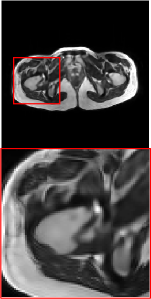

Figure 5 provides the qualitative comparison of the various methods on the four datasets at a scale of 4. The top, second, third, and bottom rows are the SR results under the FastMRI, clinical brain, clinical tumor and clinical pelvic datasets, respectively. The red boxes indicate the zoom-in region of complicated anatomical structures along with their corresponding error maps. Note that the brighter textures in the error maps, the lower the quality of the reconstructed images. As can be seen, compared to methods based on Transformers and CNNs, diffusion-based methods like DisC-Diff and DiffMSR (Ours) are capable of reconstructing high-realistic images with promising reconstruction metric scores (PSNR and SSIM). Nevertheless, while DisC-Diff can reconstruct high-precision MR images, it does not preserve the structure present in the original HR images, introducing some additional information that can affect medical diagnosis. In contrast, our method combines DM and PLWformer, which can preserve the original image’s structure while restoring high-frequency information.